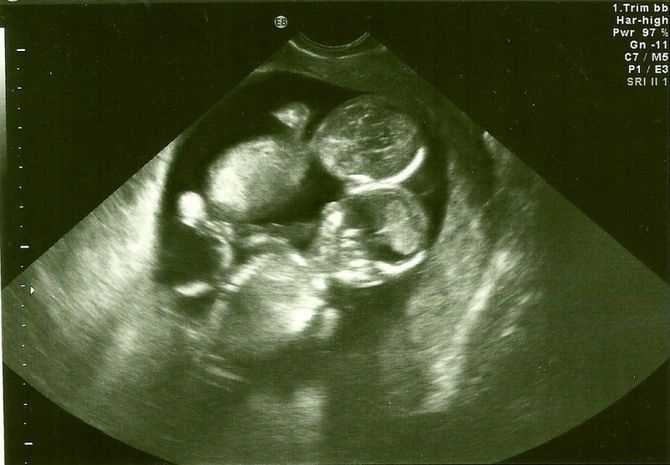

Kate, ohromená mateřskými city, naprosto šťastná, šla k lékaři. Lékařka, která zná tuto rodinu už dlouho, žertuje: „Možná tam máte znovu dvojčata?“ V Kateině lůně byla opravdu dvě srdce. Tato zpráva však bohužel nebyla jediná pro tento den.

Embrya se oddělila až po 8-13 dnech oplodnění. To znamenalo, že mezi těmito dvěma dětmi nebyla žádná ochranná membrána. Za pár dní se z nich mohla stát i siamská dvojčata. Ale to je polovina problému! Při takovém monochorialickém těhotenství by se pupečníková šňůra jednoho dítěte mohla zamotat s druhou, což by způsobilo riziko uškrcení dítěte. Šance na život těchto dvojčat nebyla velká.